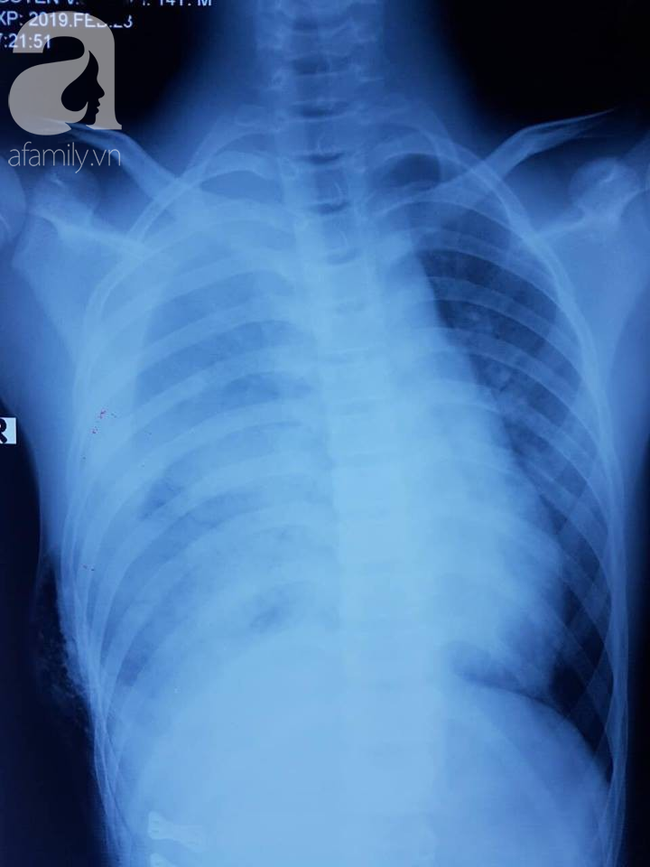

Bệnh nhân nhập viện trong tình trạng doạ sốc mất máu, đa chấn thương nặng, mạch nhanh, huyết áp xu hướng tụt, tràn máu màng phổi nhiều làm xẹp hết 1 bên phổi gây suy hô hấp nặng nề

Kết quả xét nghiệm bằng hình ảnh học cho thấy bệnh nhân bị đa vết thương, rách cơ hoành, vỡ gan, tràn máu phổi phải lượng nhiều (1.500 ml).

Ekip cũng khâu lại bết thương thấu ngực bụng xuyên thủng rách cơ hoành và hút tại chỗ khoang màng phổi hơn 1.500ml máu, sau đó dẫn lưu màng phổi phải.